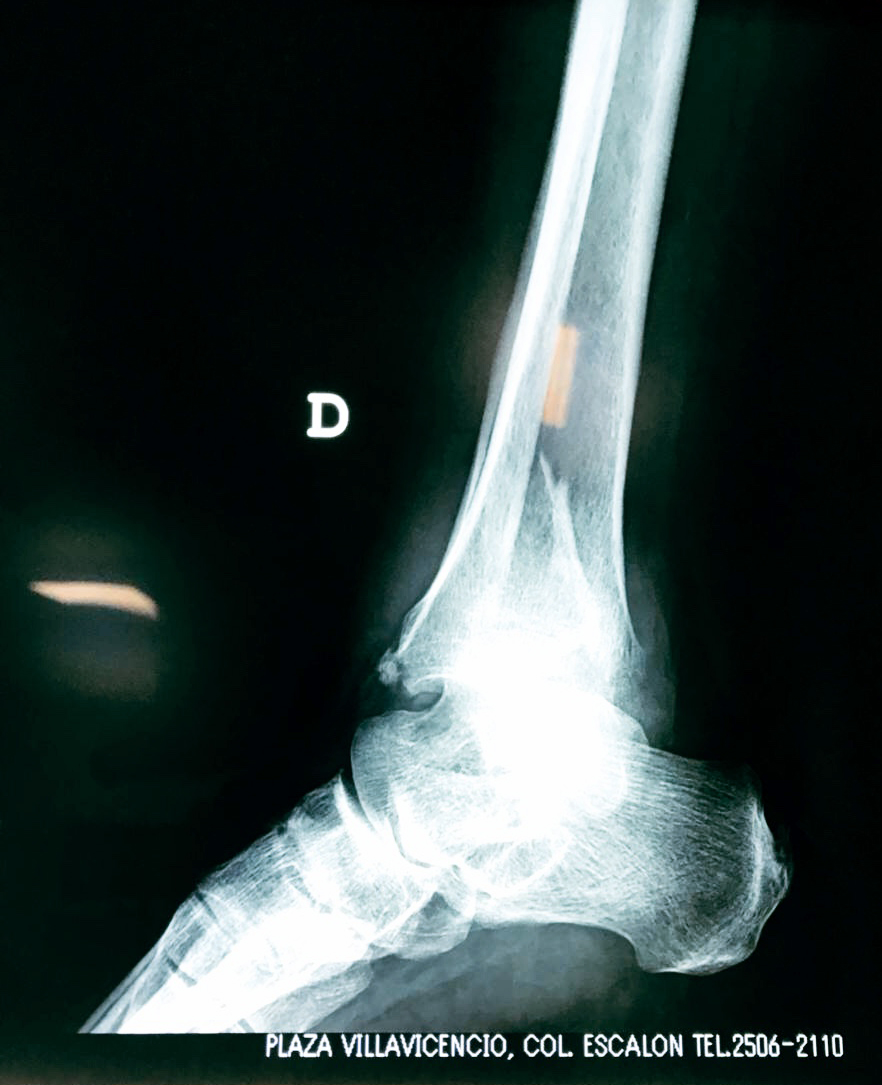

Una fractura de tobillo es la rotura de uno o más de los huesos del tobillo. Estas fracturas pueden ser:

- Los extremos de los huesos están desalineados entre sí (desplazados).

Cuando se necesita cirugía, es probable que esta implique el uso de clavijas de metal, tornillos o placas para sostener los huesos en su lugar mientras la fractura se consolida. Los elementos de soporte pueden ser temporales o permanentes.